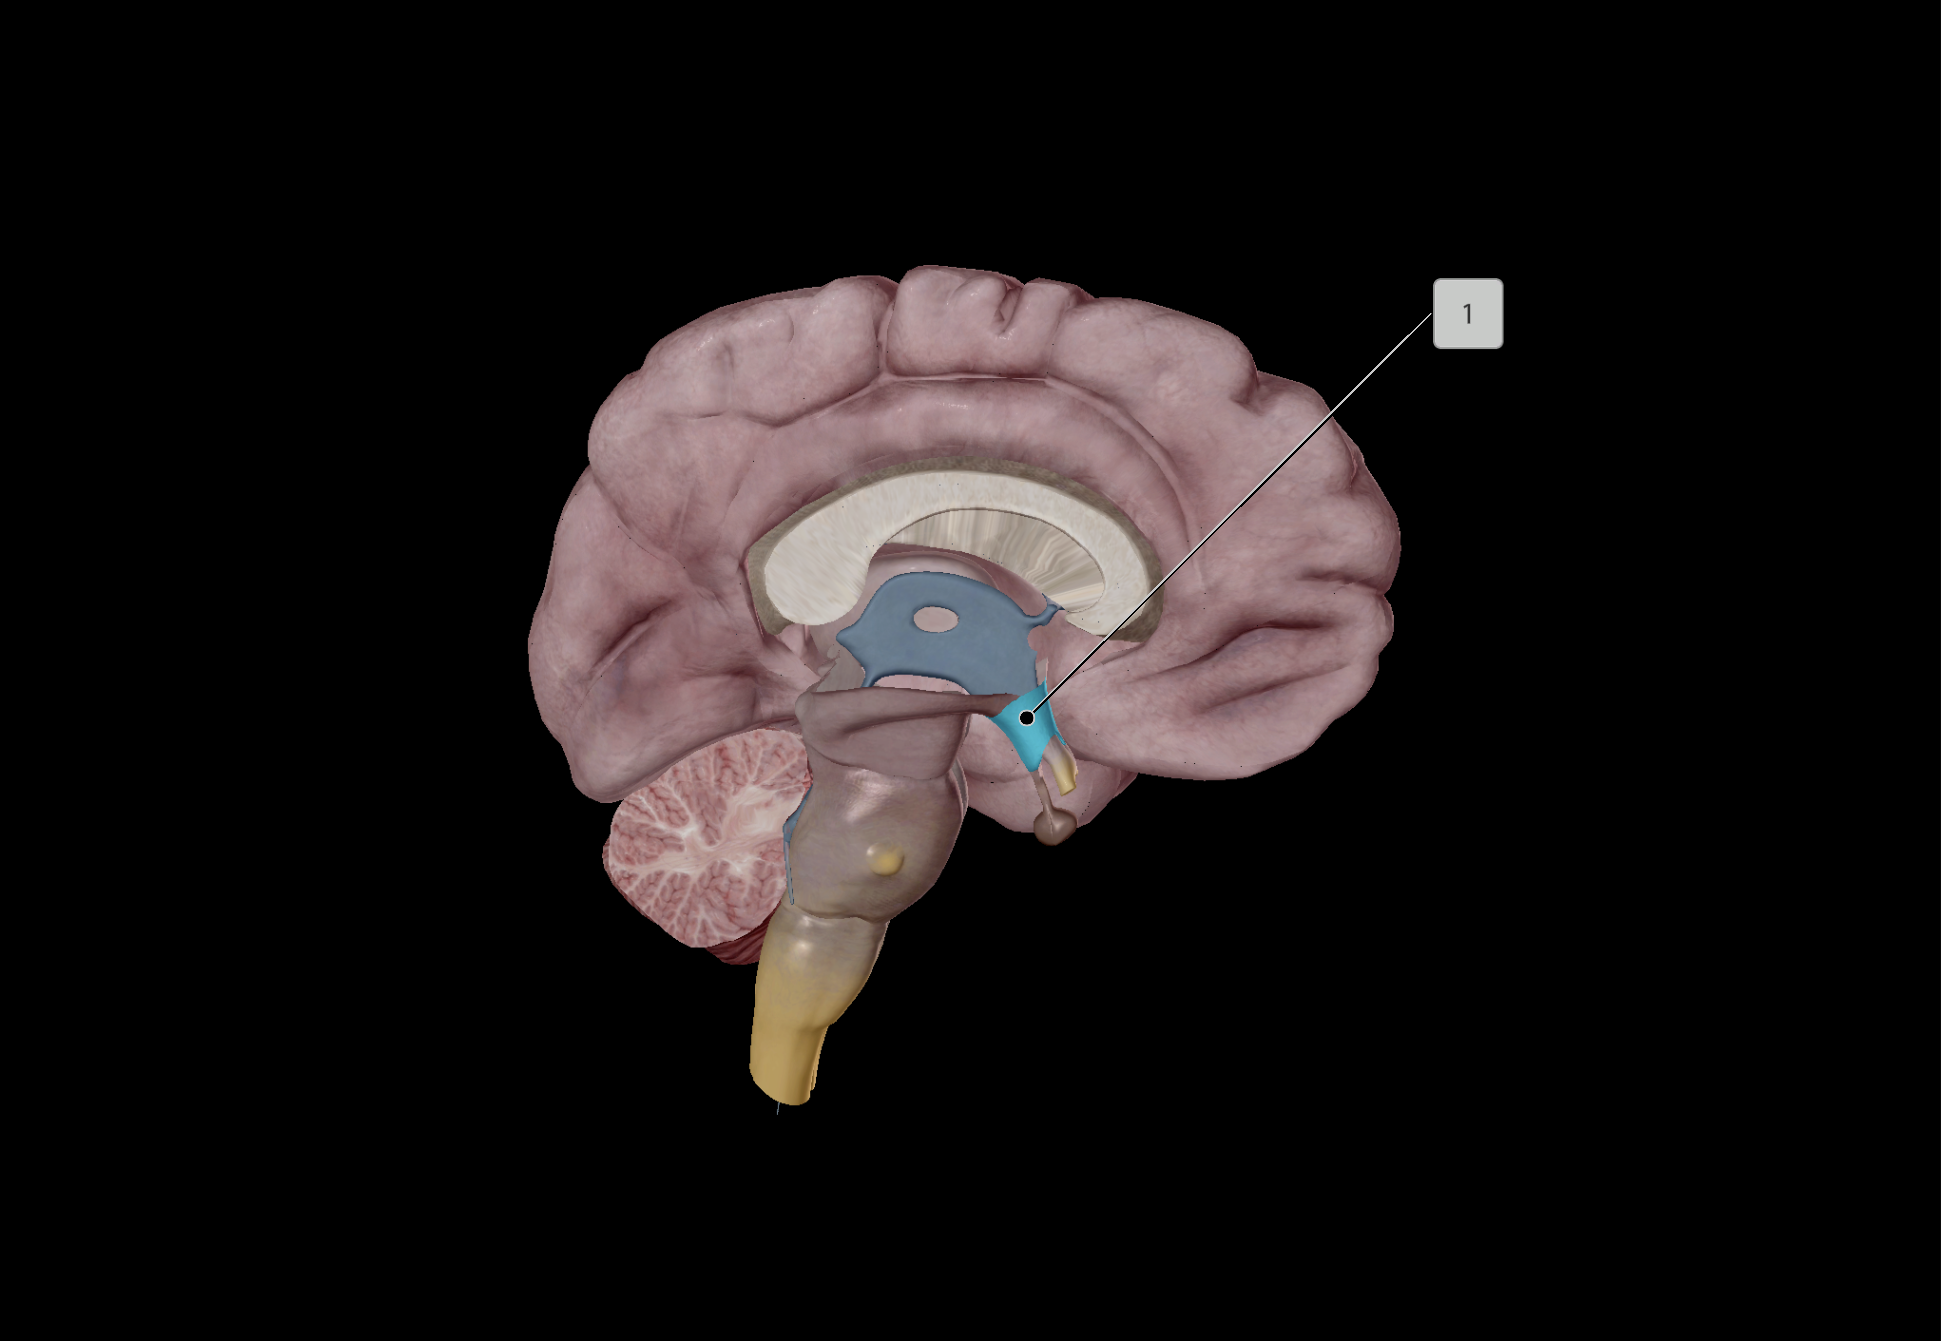

Hypothalamus